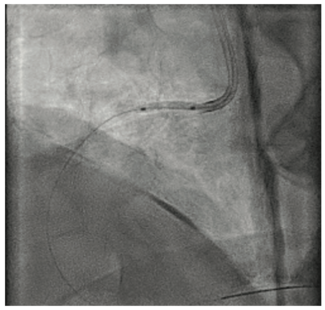

Pradnya Brijmohan Bhattad, MD; Luigi Pacifico, DO

A 54-year-old female presented with acute onset of typical substernal chest pain and was hemodynamically stable. A coronary angiogram (Figure 1/Videos 1-2, available on cathlabdigest.com) showed spontaneous coronary artery dissection (SCAD)...